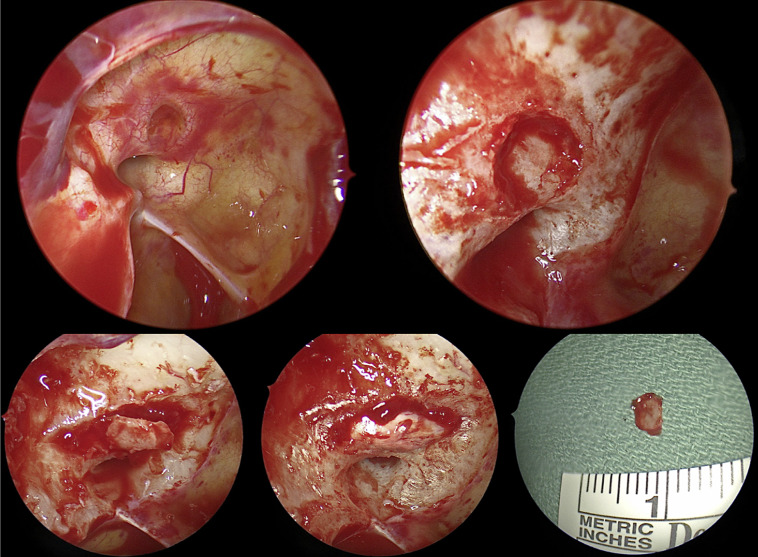

Case presentation: A 19-year old male presented with immediate total loss of vision to no light perception in the right eye after being struck on the left cheek by a lawn sign. Computed tomography and magnetic resonance imaging revealed left orbital floor fracture and right optic nerve enhancement. The patient was treated with high-dose intravenous corticosteroids and plasma exchange for a presumed inflammatory or TON. Repeat orbital imaging revealed a right OCF with bony impingement of the optic nerve. The patient underwent endoscopic optic nerve decompression; a 4 × 5 mm bone fragment abutting the optic nerve was removed. 1 month later, vision improved to hand motion.